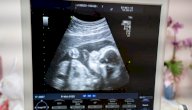

- الموجات فوق الصوتية: (بالإنجليزية: Ultrasound)، تقوم الموجات فوق الصوتية بإعطاء صور واضحة للأنسجة الرخوة ولحركتها، كما أنّها تقدّم صوراً لتدفق الدم خلال الأوعية الدموية، ويتم التصوير بجهاز الموجات فوق الصوتية عن طريق وضع جل مباشرة فوق جلد المصاب، ومن ثم استخدام الجهاز من خلال مٍجس صغير وشاشة الكمبيوتر، وهناك الكثير من الحالات التي يكشف الجهاز عنها، ومنها: أسباب الجلطة القلبية (بالإنجليزية: Heart attack)، وأسباب الشعور بالألم والانتفاخ والعدوى، بالإضافة إلى الكشف عن أمراض القلب، ومشاكل تدفق الدم، وتجلطات الدم، وتوضيح الأنسجة قبل الولادة (بالإنجليزية: Prenatal issues)، وإرشادات أخذ الخزعة (بالإنجليزية: Biopsy guidance)، وتبلغ المدة التي يستغرقها جهاز التصوير بالموجات فوق الصوتية النصف ساعة إلى ساعة واحدة.[٤]